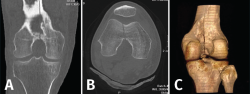

1.1. Fémur (Figuras 18 y 19)

Figura 18. A: corte de reconstrucción coronal; B: axial; y C: reconstrucción 3D de tomografía axial computarizada de rodilla: fractura longitudinal del fémur extendida al techo intercondilar.